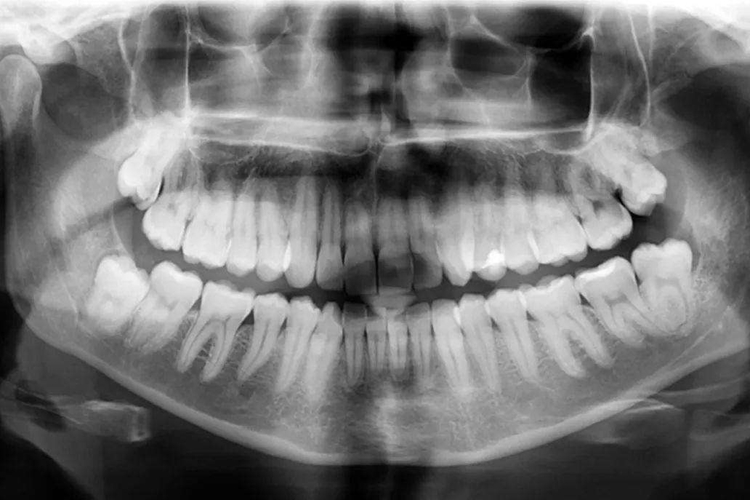

牙槽骨是上下颌骨包围和支持牙根的突起部分,骨质较疏松,且富于弹性,是支持牙的重要组织。容纳牙根的窝称牙槽窝,在冠方的牙槽窝的游离端称牙槽嵴。牙槽嵴的形态在前牙区为圆柱状,磨牙区为扁平状,而在颊舌侧变薄甚至消失。牙槽骨从X线片中,可以观察到邻间牙槽骨的高度和外形。

牙槽骨是高度可塑性组织,也是全身骨骼中变化最活跃的部分,它的变化与牙的发育和萌出、乳牙替换、恒牙移动和咀嚼功能等均有关系。生理状态下,牙咬合面及邻接面的磨耗而不断发生生理性的移位,牙槽骨也随之产生吸收和增生的改变。牙槽骨的高度可塑性,是临床上进行错(牙合)畸形矫治的生物学基础。